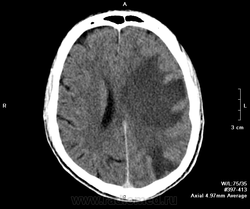

Мужчина, 40 лет. Поступил в тяжелом состоянии. В анамнезе туберкулез легких, на учете. Было высказано предположение и туберкуломах головного мозга. Нейрохирурги активно возражали, они были уверены, что это метастазы.

КТ с контрастом:

Через пару месяцев после противотуберкулезного лечения пришел на контроль на своих ногах и с его слов: "прекрасно себя чувствует". Контратировать не стали, т.к. с венами большие проблемы. Видно не без вредных привычек мужчина. Возможно появиться еще на контроль через несколько месяцев.